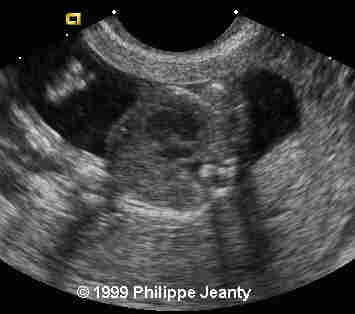

17-year-old primigravida.

This examination is obtained at 18 weeks amenorrhea.

What is your suspected diagnosis ? How would you confirm it ?

Very few, however, made the most crucial observation: the great disproportion between the head and abdomen. That disproportion is very typical of triploidy (see the lecture on aneuploidy for another example) and I know of no other conditions where such a big difference exist without a concomitant intracranial anomaly such as hydrocephaly, or teratomas… Of course, one of you will come up with a great differential diagnosis and then we will learn even more !

Teaching point: A head much greater than the abdomen is a strong sign of triploidy.

Although commonly encountered in spontaneous abortions, triploidy is rarely seen in fetuses surviving beyond mid-pregnancy. Mid-trimester sonographic findings in three triploid fetuses are described and compared with those reported in six prior cases. While sonographic characteristics are variable, common features include: 1) second trimester-onset fetal growth retardation with a reduced growth potential pattern of anthropometric growth, 2) body asymmetry with relative macrocephaly and an elevated head:abdominal circumference ratio, 3) hydrocephalus, 4) oligohydramnios, and 5) an abnormally large and/or hydropic placenta (in cases of paternal origin). Genetic amniocentesis and amniotic fluid chromosome studies should be performed when ultrasound findings suggestive of fetal triploidy are identified.